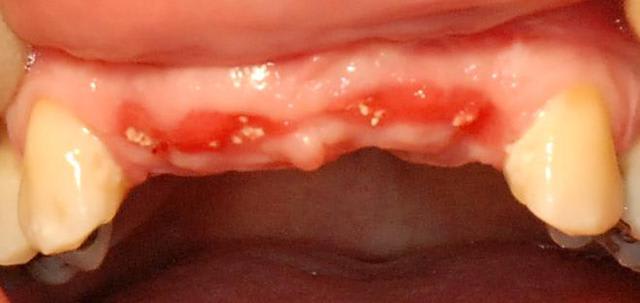

la suite, à 5 semaines ça semble pas trop mal.

Img 9148 lqmsnj - Eugenol

Img 9149 fjys6t - Eugenol

Img 8465 fqhxid - Eugenol

je trouve aussi cette technique tres elegante et pratique

Question cependant ou a tu prelevé meme sectuer que l'avulsion pour centraliser les douleurs post op ou bien de l'autre cote?

dans le même secteur, je suis sadique mais quand même.

C'est joli joli, comment tu as fait pour éviter la nécrose du greffon en site 6 ?

rien de spécial, pareil que les autres mais j'ai quand même eu une nécrose au moins superficielle sur tous les greffons.

Ce qui est normal et systématique.